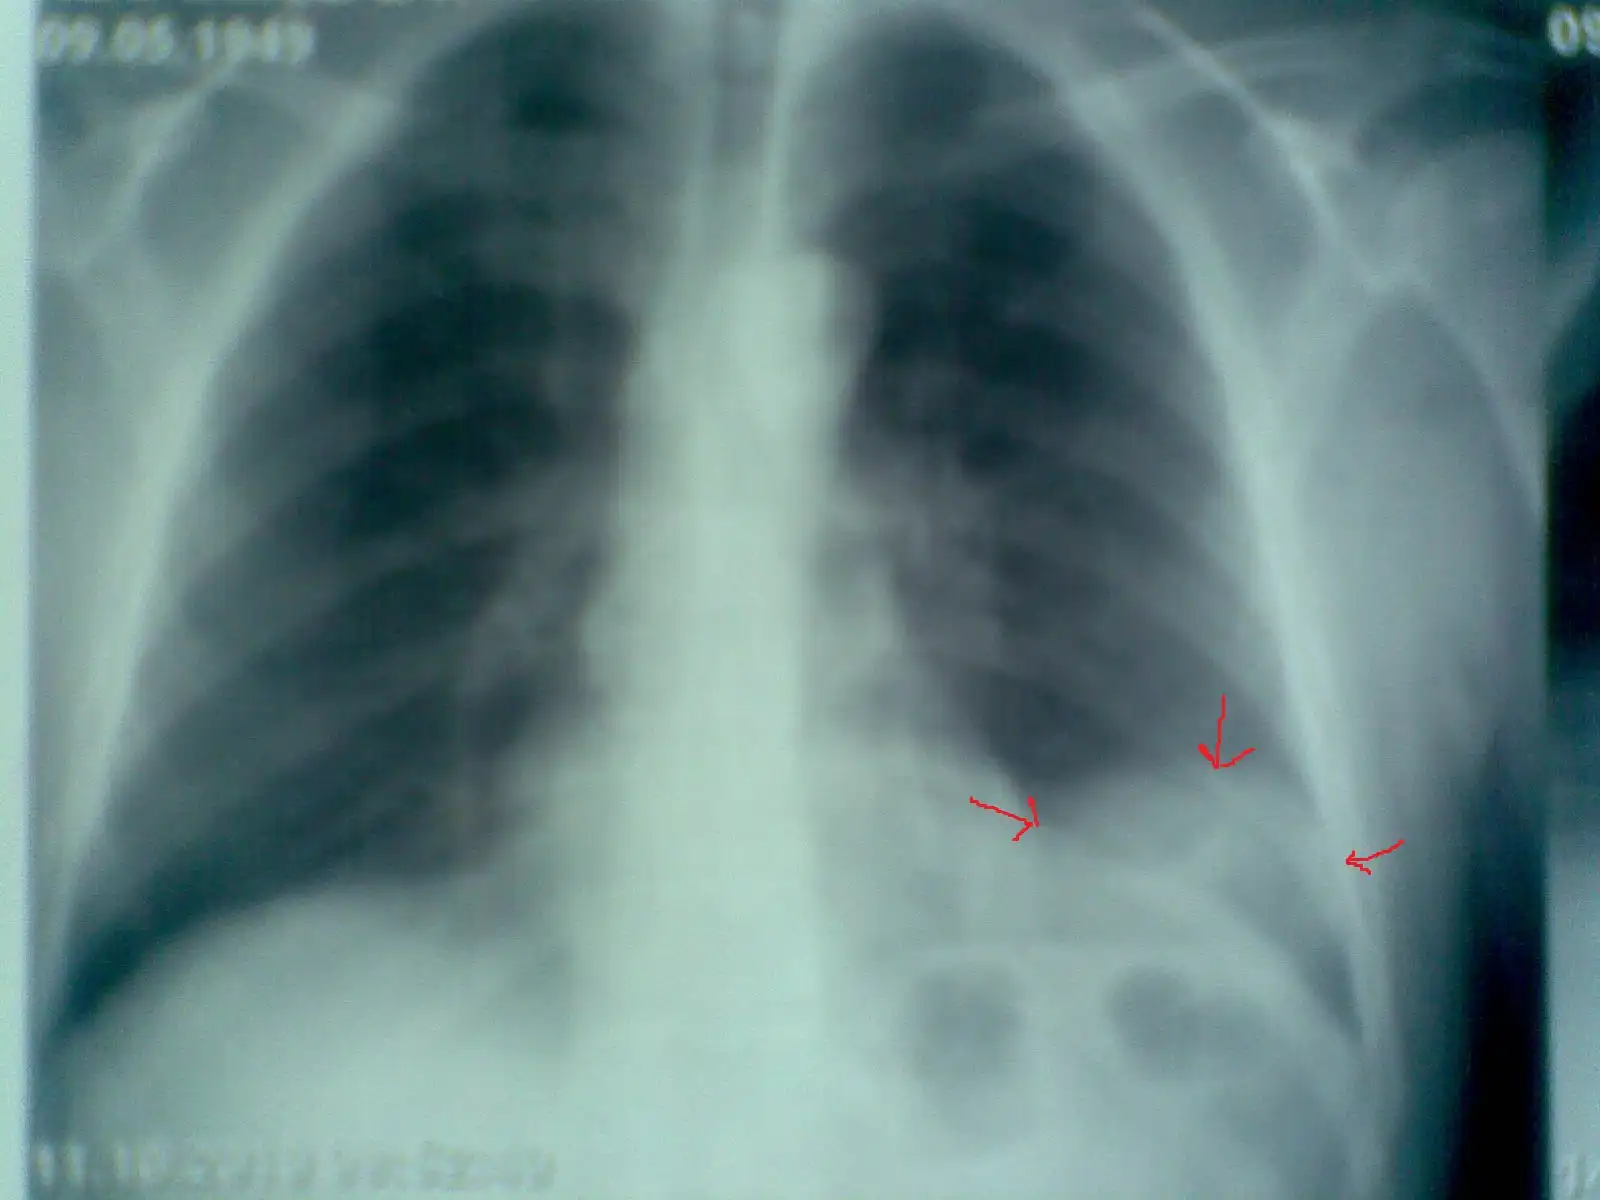

Пациент № 1:

Пациент №2: